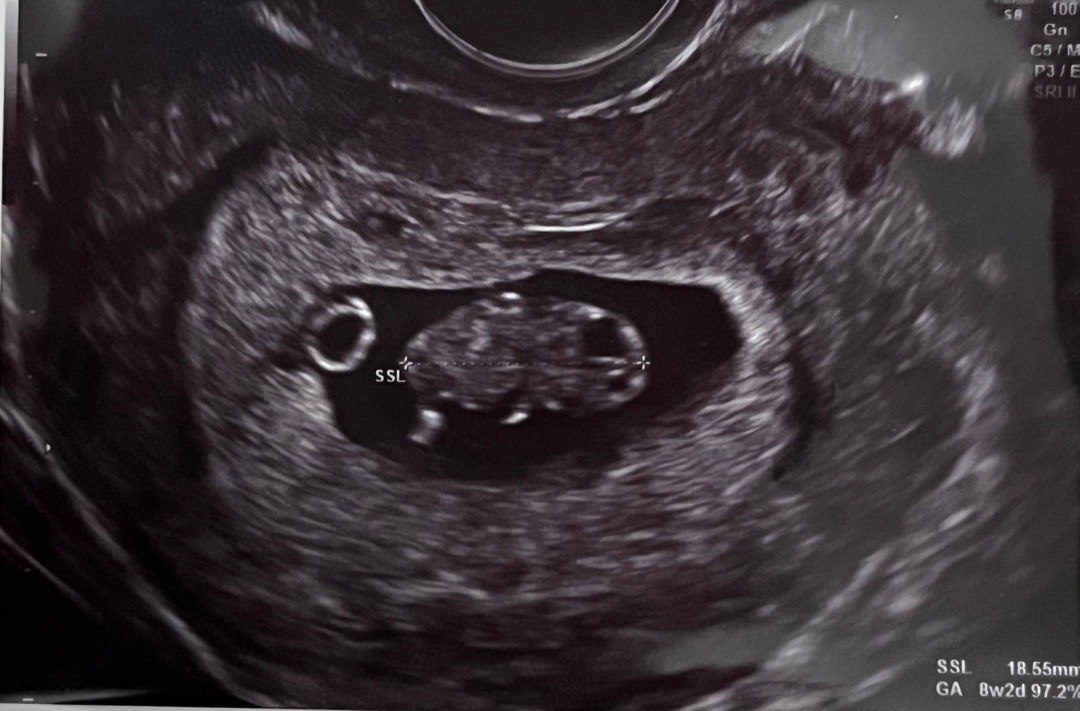

15주 아기 성별 각도법🥹

그저께 다녀왔는데 외국 살아서 그런지 쓰리디 초음파도 없고.. 한달에 한번 검진가고있어요 그저께 가서 성별 알수있을줄 알고 남편이랑 긴장 햇는데 또 한달 더 기다려야해요😭 선배님들 보시기에 딸일지 아들일지 보이시나요? 힌트 부탁드려요 너무 궁금해요😳😳 심지어 15주 사진도 안찍어주셔서.. 사진은 8주때 사진이에요😅😂

각도법 안보이는 사진이에용

답글 감사해요!😍 8주때 사진으로 다시업로드 햇어요! 이사진은 각도법이 보일까요?

8주는 너무 아가아가때라 안보일때에용 ㅠㅠㅠ 그때는 젤리곰 볼때니까용